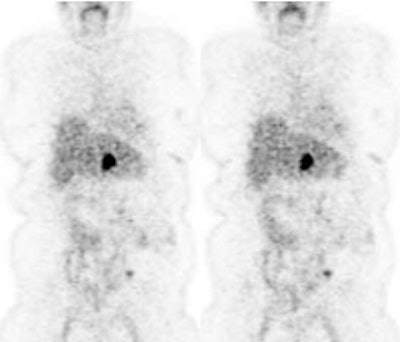

Initial staging for colorectal carcinoma: The patient below presented for evaluation of colorectal carcinoma. The CT scan demonstrated a large liver mass (red arrows) compatible with metastatic disease. The patient's cecal mass (black arrow on PET scan) was not detected on the CT study (white arrow). No other lesions were identified on the PET scan. |